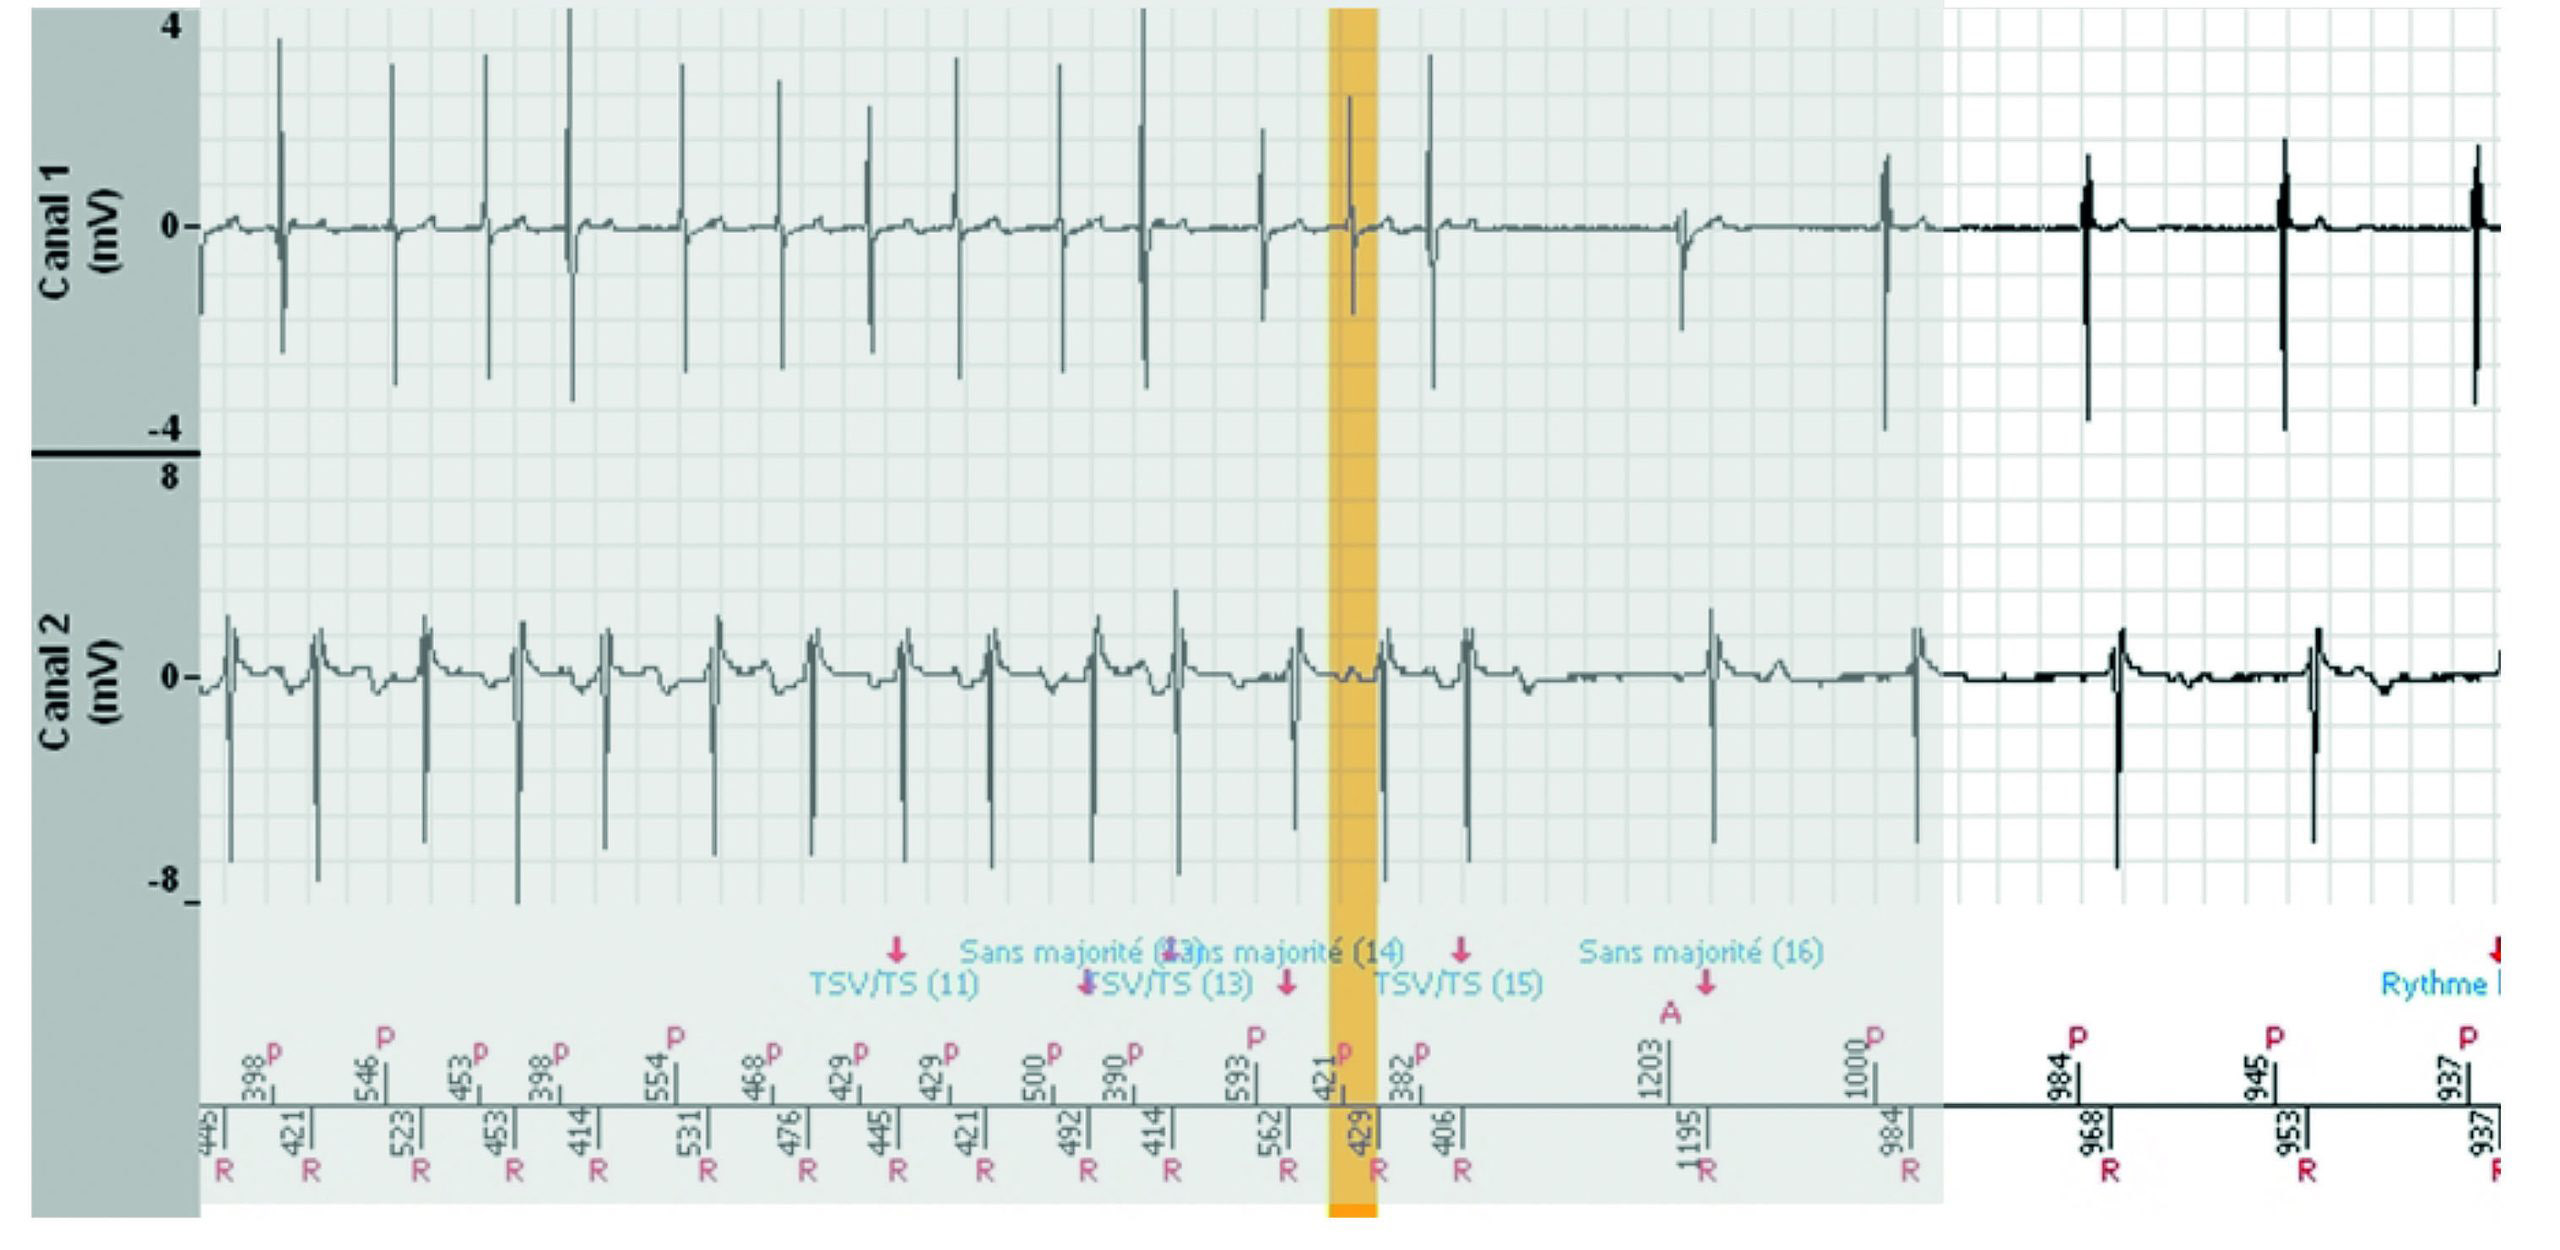

Tachogramme

EGM

Les zones ombragées sont les portions de l'EGM qui sont les répétitions de la fin de l'image précédente.

- Le tachogramme démontre des extrasystoles auriculaires et ventriculaires pendant un rythme sinusal conduit.

- La tachycardie est précédée d'un triplet ventriculaire avec une probable conduction rétrograde, suivie d'une déstabilisation immédiate du rythme auriculaire qui initie une tachycardie auriculaire instable et répercutée dans le ventricule, conduisant au diagnostic de TSV. Chaque variation de l'intervalle P'P’ induit la même variation de l'intervalle RR correspondant. La tachycardie est bien contrôlée par l'oreillette.

- Le diagnostic est non majoritaire lorsque le rythme entre ou revient dans la zone lente (non tachycardique) pendant au moins 3 cycles sur 8 (mais moins de 6), puis redevient instable avec un diagnostic de TSV jusqu'à la fin de l'épisode.

- Aucune thérapie n'a été délivrée.